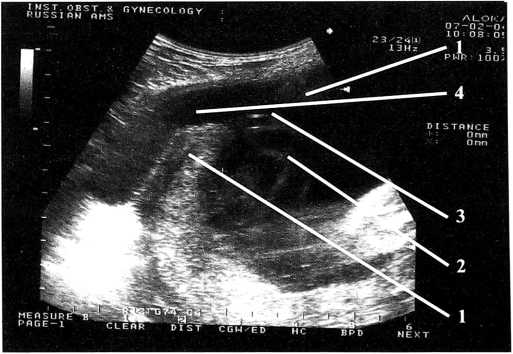

В матке определяется один живой плод в головном предлежании. По фетометрическим данным соответствует 30/31 неделям беременности. В верхней трети передней стенки матки имеется дефект миометрия 6,0×5,0 см. За пределами матки определяется часть амниотической полости 8,0×5,0 см, в котором находится петля пуповины, при шевелении в него выходит ножка плода (рис. 1,2).

Рис. 2. Ультразвуковая сканограмма: 1 — миометрий передней стенки матки; 2 — пуповина; 3 — дефект стенки матки; 4 — плодный пузырь вне полости матки